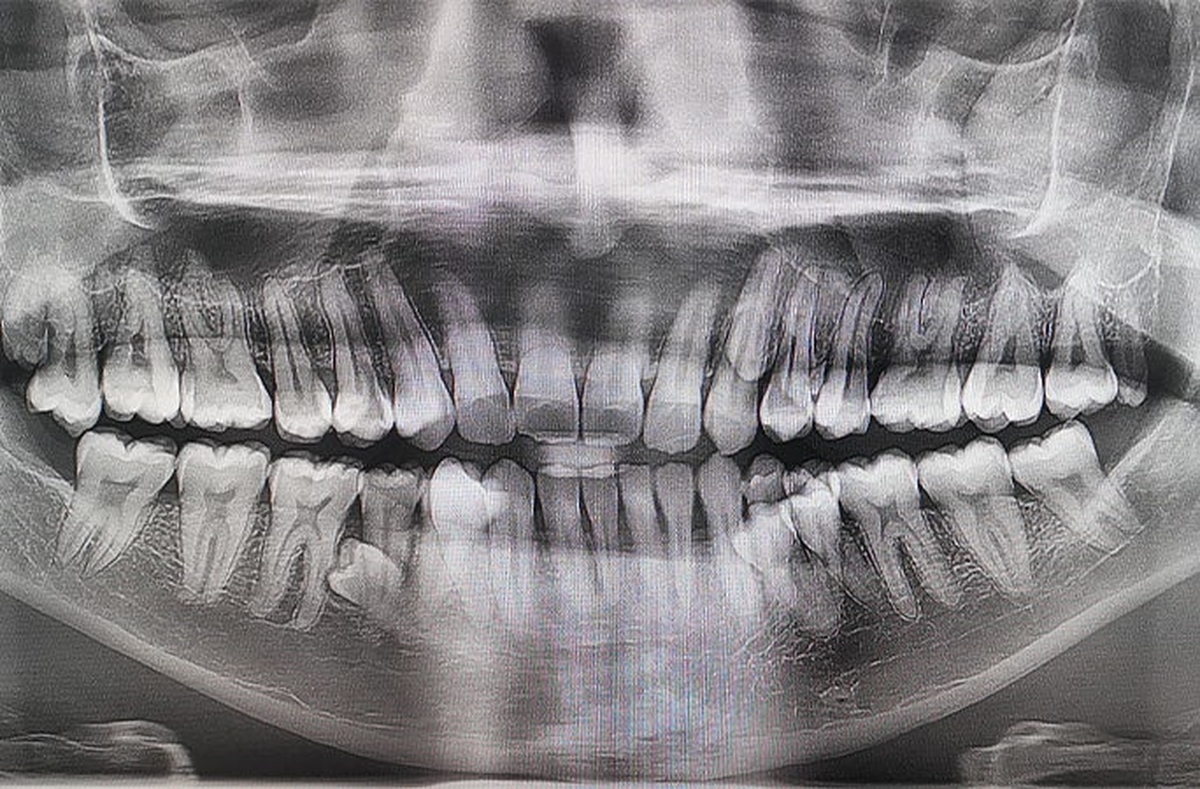

기록 인정을 위해 프라탑은 두 명의 치과의사로부터 정밀 검진을 받았다. 검진 결과 42개의 치아가 확인됐으며, 추가로 잇몸 속에 매복된 치아 2개도 발견됐다.

0000106072_002_20260311230111014.jpg치아 엑스레이 검사 사진 / 기네스 세계기록 제공